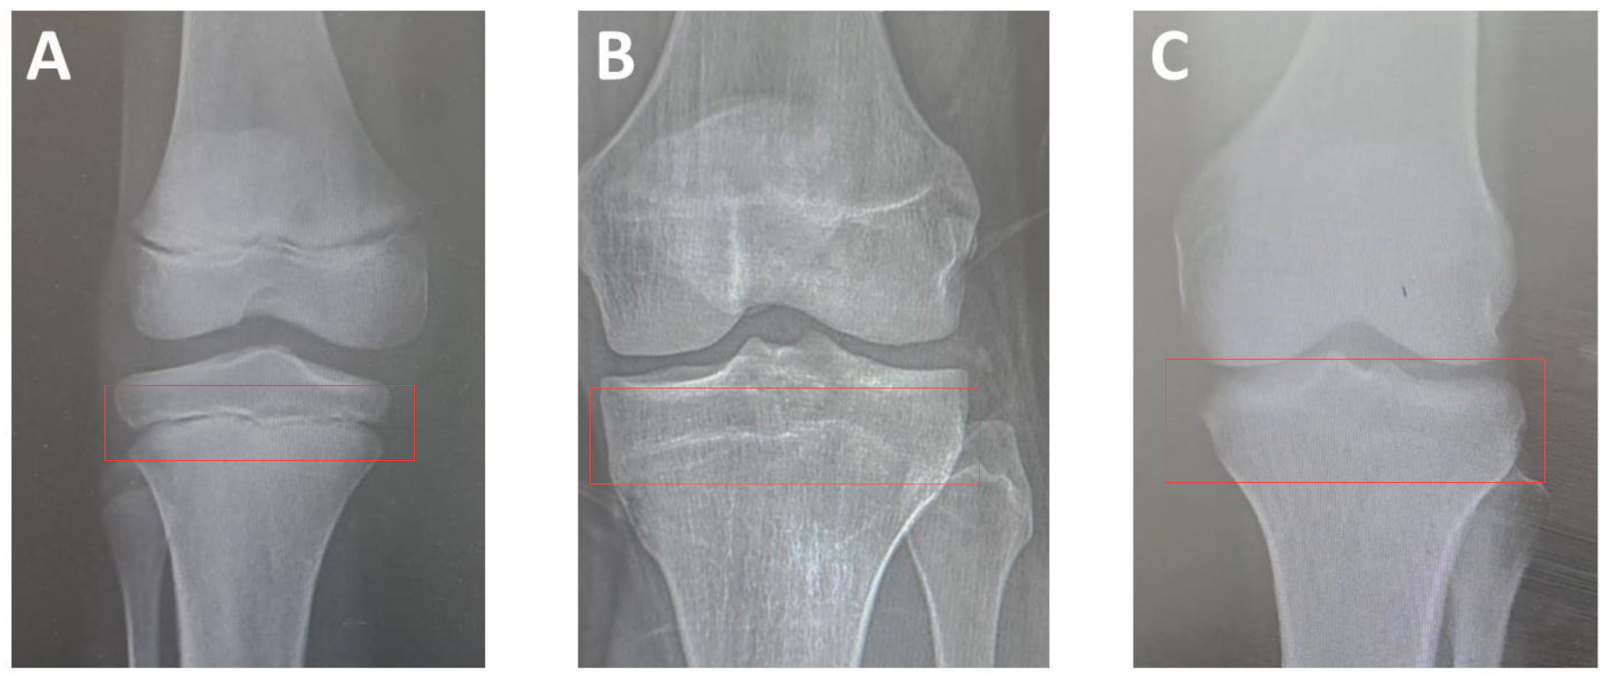

The growth plates in your knees are closed

(A being super open, C being fused)

I made a guide on the radiology behind this stuff recently, but you likely won't grow any more, even on 8iu of hgh